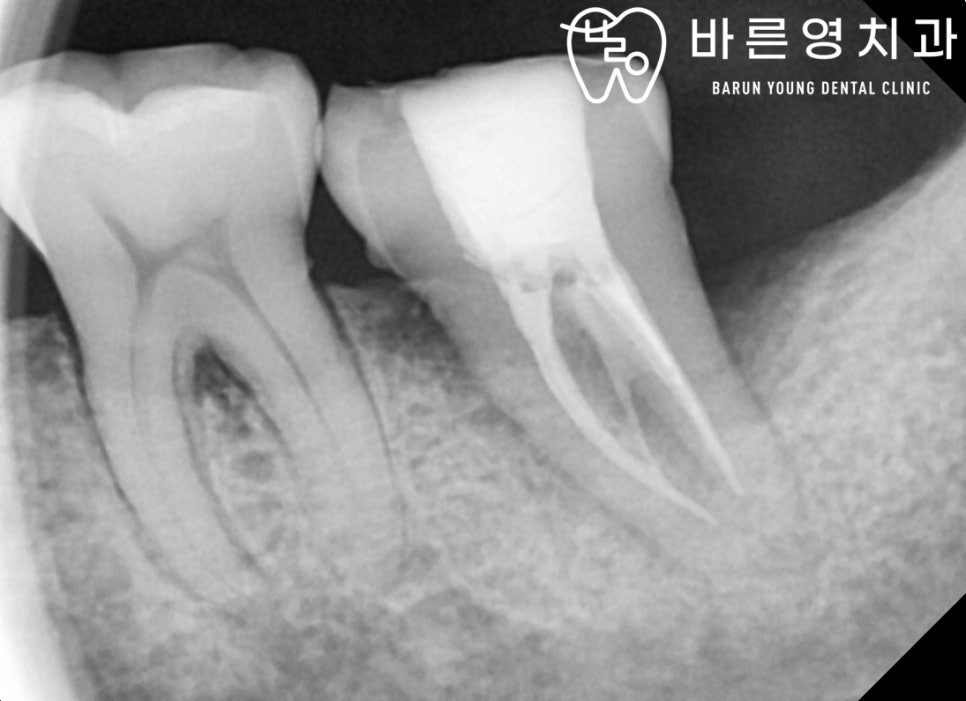

바른영치과 신경치료 사례

만약 위 단계까지 옥수역치과 충치치료를 통해 충치를 제거하지 않아 더 악화되면 충치는 상아질을 지나 치수염(치아신경)까지 퍼지게 되는데요. 이 시기는 이미 충치가 치아신경을 오염시켜 염증이 발생한 상태이기 때문에 보다 난도 높은 옥수역치과 신경치료를 진행하게 됩니다.

오염된 신경을 제거하고, 해당 빈 공간에 보충재를 채우는 신경치료 단계는 이미 자연치아가 절반 이상 손상된 상태이기 때문에 보충재만 채워서는 자연치아 저작기능을 수행하기에는 많이 약해진 상태입니다. 하여 신경치료 이후에는 남은 자연치아를 보호하고 치아기능을 제대로 수행할 수 있도록 치아모형의 보철을 씌우는 크라운 치료를 진행하게 됩니다. 이 크라운 치료가 바로 우리가 흔히 말하는 ‘금니를 씌운다’고 표현하는 치료이며, 크라운의 종류는 금니 뿐만 아니라 치아와 심미적으로 거의 흡사하고 강도가 높은 지르코니아까지 다양합니다.

즉, 충치치료 단계 중 신경치료는 자연치아를 살릴 수 있는 마지막 단계이기에 부득이한 경우가 아니라면 신경치료를 통해 남은 자연치아를 살리고 보존하는 것이 현명합니다.